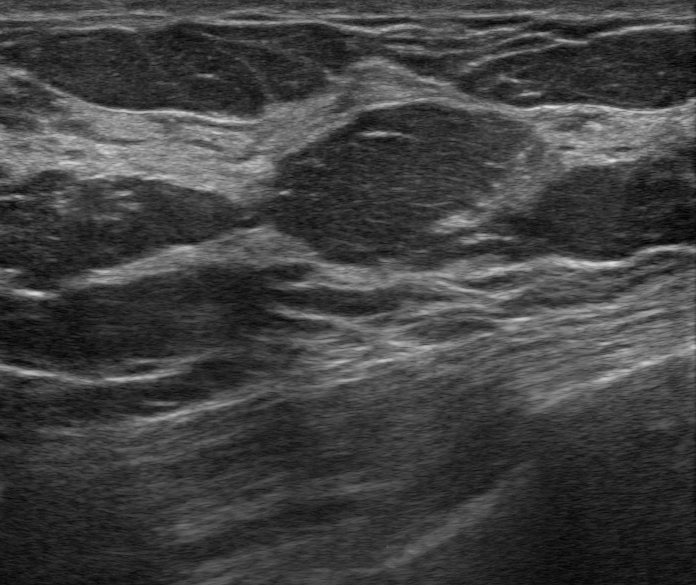

乳房組織